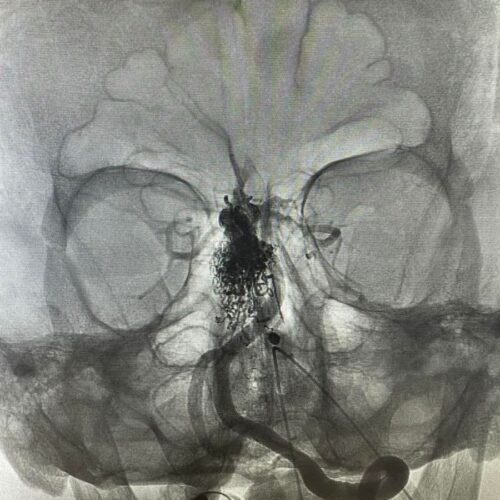

Δια ζώσης συμμετοχή των φοιτητών του Πανεπιστημίου Πατρών σε εξειδικευμένες τεχνικές ενδοαγγειακής αντιμετώπισης αγγειακών δυσπλασιών του κεντρικού νευρικού συστήματος.

Στην επέμβαση συμμετείχαν ο Καθηγητής Ενδοαγγειακής Νευροχειρουργικής Κος Β. Παναγιωτόπουλος, ο Καθηγητής Επεμβατικής Νευροακτινολογίας κος Π. Ζαμπάκης, ο επιμελητής επεμβατικής ακτινολογίας κος Μ. Θεοφάνης και ο αναισθησιολόγος κ. Γούδας.